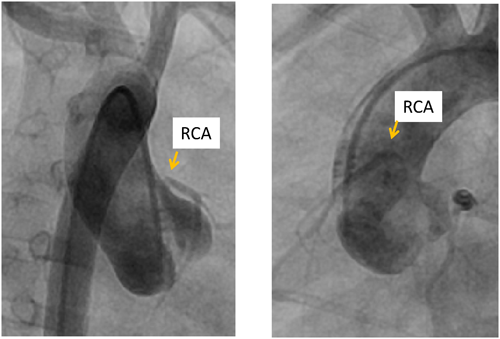

ファロー四徴症の根治手術ではその多くで右室流出路拡大手技が必要であり,有効な右室流出路狭窄解除を行うにあたり冠動脈の走行が影響することがある.文献的にはファロー四徴症の5~12%に冠動脈の走行異常が認められるとされており15, 16),左前下行枝が右冠動脈から分枝するもの,単一冠動脈で左前下行枝または右冠動脈が右室流出路を横切るもの,また重複左前下行枝などが報告されている(Fig. 12).これらの症例ではtrans-annular patch法はできないため,肺動脈狭小弁輪症例では右室肺動脈導管を用いたラステリ型手術の適応である.ファロー四徴症における冠動脈走行異常の頻度は少なくないため術前のカテーテル検査では大動脈造影は必須である.また単独の心室中隔欠損症でも右冠動脈の高位起始(Fig. 13)などの異常を認めることもあり,剥離操作や大動脈遮断に際して注意が必要である.

Pediatric Cardiology and Cardiac Surgery 32(2): 114-121 (2016)

Fig. 12 Coronary artery anomaly in the tetralogy of Fallot

Left anterior descending (LAD) is originated from the right coronary artery.

Fig. 13 Abnormally elevated origin of the right coronary artery in isolated VSD